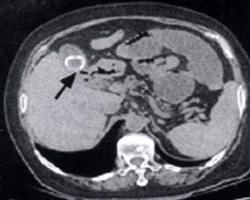

腹部X線檢查可有4個特徵:

1.腸梗阻由於結石大部分不大且圓滑,在腸道可逐漸下移故梗阻多為不完全性,並梗阻點多改變,但小腸低位,回盲瓣口常為梗阻點,梗阻多在小腸,結腸也可發生梗阻。

2.膽囊、膽管內積氣,以膽管積氣較多,可為一粗管狀,也可有小分支,由於梗阻前多有膽管梗阻,故膽管較正常粗大,通常較Oddi括約肌鬆弛、膽道蛔蟲帶入的氣體或其他原因,與腸道瘺管、膽系-胃腸吻合等引起的膽管積氣,顯得更粗大,以資鑑別。

3.腸內膽石,約50%的膽石可在X線下顯影,有的顯影較淡,所以,膽石性腸梗阻約半數只有腸梗阻和膽系積氣表現,而未見膽石。

X線檢查有4種徵象:①部分性或完全性腸梗阻的表現;②膽道積氣;③異位的即在膽系外的區域有膽石影;④鋇餐或鋇灌腸檢查,見鋇劑進入膽道或直接襯托出膽道的結石影。